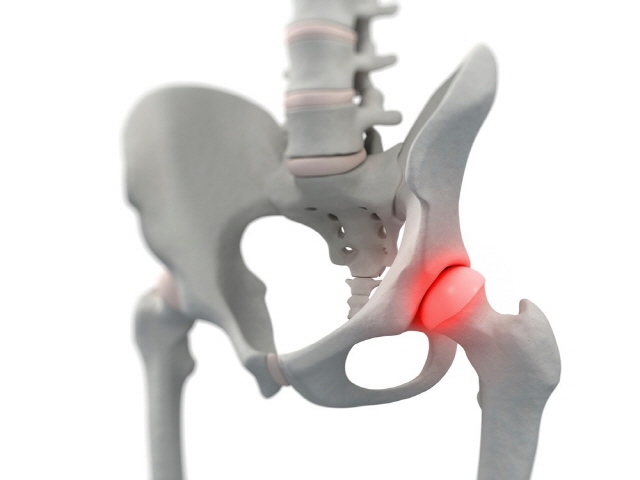

고관절이란?

고관절은 엉덩이관절이라고도 불리우며, 보통 알고있는 골반위치에 있고, 공처럼 둥글게 생긴 대퇴골두가 글러브가 감싼듯한 모양으로 비구에 맞물려 있어요.

이렇듯 고관절은 오목하게 들어간 비구와 둥근 공모양의 대퇴골두로 이루어져 있으며 골반과 다리를 이어주는 우리 몸의 핵심 관절인데요. 그리고 고관절은 골반을 통해 전달되는 체중을 지탱해주고 걷기와 달리기같은 다리 운동들을 가능하게 해주는 관절이기도 해요.